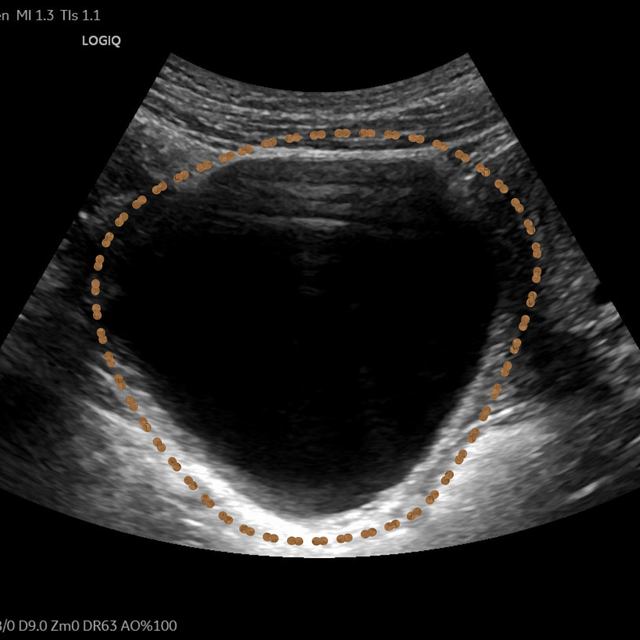

无独有偶,家住城东的赵老先生时感右腰酸胀,到附近医院检查后发现右肾有一个7.0*6.4cm的巨大囊肿,这成了老赵的一块心病。儿女们也为老父亲的囊肿四处求医,最后慕名来到昆山市中医医院超声介入门诊寻求帮助。

▲患者超声影像

超声介入张轶亮主治医师了解老赵的病情后立刻为其超声检查,发现右肾囊肿确实很大,已经压迫了周围肾组织。

考虑到老赵年事已高,行动不便,王晓明副主任医师当即电话联系泌尿外科,安排其住院,并行CTU(尿路造影)、血凝等术前常规检查,第二日在局部浸润麻醉下进行超声引导下肾囊肿穿刺抽液硬化治疗。

整个治疗过程不到30分钟。老赵下手术台后连连称赞现在的治疗技术真厉害,一点都没感到疼痛。术后观察24小时无明显不适即出院回家。

一个月后,老赵复查发现右肾囊肿已经缩小到1cm以内,体积缩小率高达99%,老赵表示非常满意。